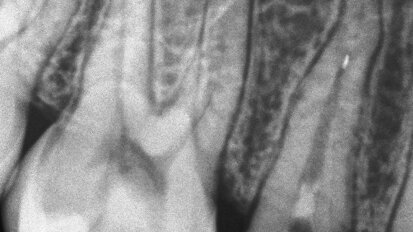

DIAGNOcam – nova, laserska metoda aproksimalne dijagnostike karijesa sa mogućnošću snimanja

PROMOTIVNI TEKST PREUZET IZ: KaVo VISION POLSKA 2013 Rendgenski snimci zuba, takozvani BiteWings, trenutno predstavljaju „Zlatni standard“ ...